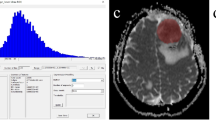

Furthermore, we calculated the contrast-to-noise ratios (T2CNR, T1CNR, DWICNR) in reference to Hayashida et al. [20] by the formula: \(\frac{(\mathrm T2^{\mathrm{STmean}}\;-\;\mathrm T2^{\mathrm{WM}})}{\mathrm T2^{\mathrm{noise}}}\) (only exemplarily shown for T2CNR). ROI placements and calculations are displayed schematically in Fig. 2.

Workflow of region of interest definition and score calculation. Exemplary scheme of region of interest (ROI) placements and calculations on a right parieto-occipital brain metastasis. a–b Signal intensities of the solid tumour in the T2- (a) and T1- (b) weighted sequences were assessed by five ROIs. c–d The limited spatial resolution of the DWI (c) and ADC (d) parameter maps available allowed the assessment by no more than three ROIs. We documented the average of these ROIs (T2mean, T1mean, DWImean, ADCmean). a–d Same-sized uniform ROIs were also drawn in the corresponding normal-appearing white matter of the contralateral hemisphere as reference values (T2WM, T1WM, DWIWM, ADCWM). Normalised values were established as ratios to the reference ROI yielding (nT2mean, nT1mean, nDWImean, nADCmean). Further, we drew one ROI in the surrounding air outside the head taking its standard deviation as noise signal (T2noise, T1noise, DWInoise). For all ROI measurements, we always selected areas without obvious signs of bleedings (e.g. susceptibility artefacts in T2*-weighted images)